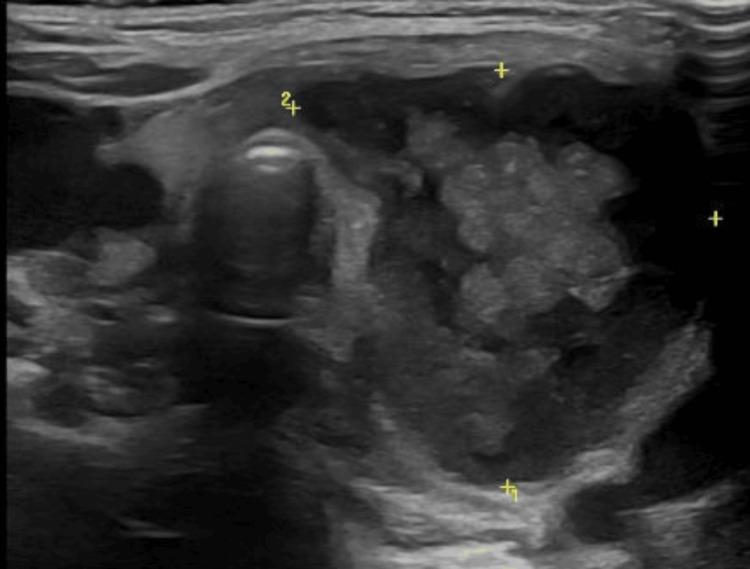

Neck stiffness is a common clinical sign in children presenting to the emergency department that may indicate a wide variety of diagnoses. Acute suppurative thyroiditis (AST) is an infection of the thyroid gland caused by a bacterium, virus, or, less commonly, fungus. It presents as an acute or subacute development of an anterior cervical mass, with associated inflammatory signs. The pressure upon neck muscles may be reflected as a limitation of cervical mobility. AST is often preceded by an upper respiratory tract infection, and pyriform sinus fistula is the most common predisposing factor. It is particularly uncommon in the pediatric age, with limited cases reported in the literature. Therefore, a heightened suspicion is required for proper diagnosis and timely intervention, due to its high mortality. Prompt treatment with broad-spectrum parenteral antibiotic therapy and drainage is mandatory to prevent the numerous complications associated, namely, mediastinitis and sepsis. We report the case of a two-year-old female child admitted with a two-week history of intermittent high-grade fever and sore throat, followed by prostration and limitation in neck movement on admission. Examination revealed neck stiffness with positive Kernig and Brudzinski signs. The laboratory tests showed elevated inflammatory parameters. Cranial computed tomography (CT) scan and lumbar puncture were normal. On day 2 after admission, an anterior cervical mass with slight signs of fluctuation was detected. Ultrasound was compatible with a hemorrhagic/overinfected thyroid nodule, and the patient was started on broad-spectrum antibiotics. Due to clinical worsening, a cervical CT scan was performed, which documented a thyroid abscess with extension into the retropharyngeal space. She underwent surgical drainage, and  and mixed anaerobes were isolated, sensitive to ongoing antibiotherapy. On multidisciplinary follow-up, an esophageal barium study, laryngoscopy, and cervical magnetic resonance imaging (MRI) were performed, revealing no anatomical defects. AST is a rare disease in children, but potentially fatal, so its early recognition and treatment are essential. We aim to draw attention to this disease and its differential diagnosis to reduce the associated morbimortality.

颈部僵硬是儿科急诊中常见的临床体征,可能提示多种诊断。急性化脓性甲状腺炎(AST)是由细菌、病毒或较少见的真菌引起的甲状腺感染。它表现为颈前部肿块急性或亚急性发展,并伴有相关炎症体征。颈部肌肉所受压力可能表现为颈部活动受限。AST通常先有上呼吸道感染,梨状窦瘘是最常见的诱发因素。它在儿童期尤其罕见,文献报道的病例有限。因此,鉴于其高死亡率,为了正确诊断和及时干预,需要提高警惕。必须迅速采用广谱肠外抗生素治疗和引流,以预防相关的众多并发症,即纵隔炎和败血症。我们报告一例两岁女童,因间歇性高热和咽痛两周入院,入院时继而出现虚脱和颈部活动受限。检查发现颈部僵硬,凯尔尼格征和布鲁津斯基征阳性。实验室检查显示炎症指标升高。头颅计算机断层扫描(CT)和腰椎穿刺均正常。入院后第2天,发现一个有轻微波动迹象的颈前部肿块。超声检查结果符合出血性/感染过度的甲状腺结节,遂开始对患者使用广谱抗生素。由于临床症状恶化,进行了颈部CT扫描,结果显示甲状腺脓肿并蔓延至咽后间隙。她接受了手术引流,分离出混合厌氧菌,对正在使用的抗生素敏感。在多学科随访中,进行了食管钡餐检查、喉镜检查和颈部磁共振成像(MRI),未发现解剖学缺陷。AST在儿童中是一种罕见疾病,但可能致命,因此早期识别和治疗至关重要。我们旨在引起对这种疾病及其鉴别诊断的关注,以降低相关的发病率和死亡率。